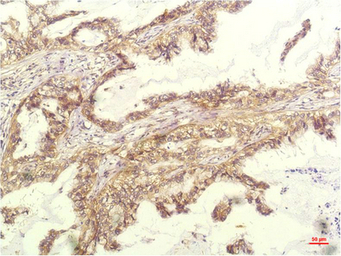

IHC-P analysis of human lung carcinoma tissue using GTX34340 CXCL8 / IL8 antibody [14E1].

Dilution : 1:200